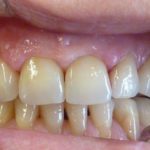

Très sévères retraits gingivaux avec fortes sensibilités et une esthétique compromise

Chirurgie de déplacement des tissus sans greffe additionnelle

Après dépose des points, le résultat est très satisfaisant